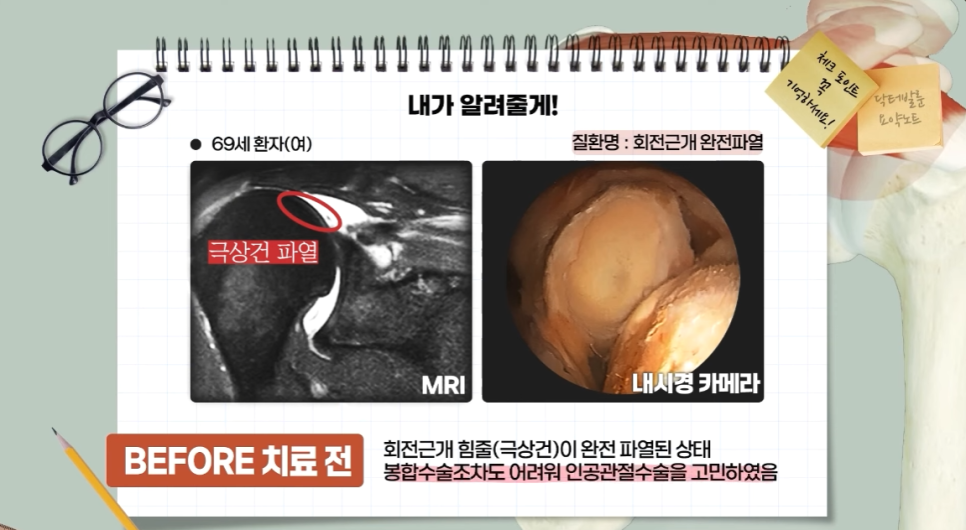

어깨통증환자 중 본인도 모르게 만성적으로 회전근개가 파열된 경우 남아있는 근육도 정상적이지 않게 약해져서 수술로 잘 봉합해도 재파열될 수 있습니다. 제대로 봉합하지 못할 수준까지 악화하면 인공관절 수술을 과거에는 많이 시행하였는데요,

회전근개 힘줄 재파열이 가장 많은 곳은 바로 극상건입니다. 이 부분은 어깨 위쪽으로 대부분의 회전근개파열 원인이 되는 곳이기도 하죠.

✔️ 처음엔 작은 파열로 시작되지만 염증이 반복되면 점점 손상되면서 완전히 파열

-🚨완전파열, 즉 광범위 파열이 관찰됨

회전근개파열이 미약하게 발생했다면 비수술 치료로도 호전을 기대할 수 있지만, 회전근개 완전파열의 경우에는 수술적 치료를 진행하게 됩니다. 파열된 어깨 회전근개가 범위가 넓거나 증상이 심한 경우, 혹은 이미 회전근개봉합술로 회전근개파열 치료를 했는데도 추후 재파열이 되어 어깨 재수술을 해야 하는 경우에는 봉합이 어려울 정도로 심하게 파열된 경우도 있습니다.

몇 년 전까지만 하더라도 회전근개 재파열이 발생된 경우라고 하면 파열 부위를 봉합하는 수술을 하거나 그 다음단계인 인공관절 수술치료만을 고려해야 하는 상황이었습니다.(역행성 인공관절 치환술이라고도 많이 알고 계십니다.) ➡💦 ️

하지만 젊은 환자분들 중 60세 미만의 환자분들 같은 경우, 인공관절치환술의 예후가 좋지 못한 분들이 많았습니다.